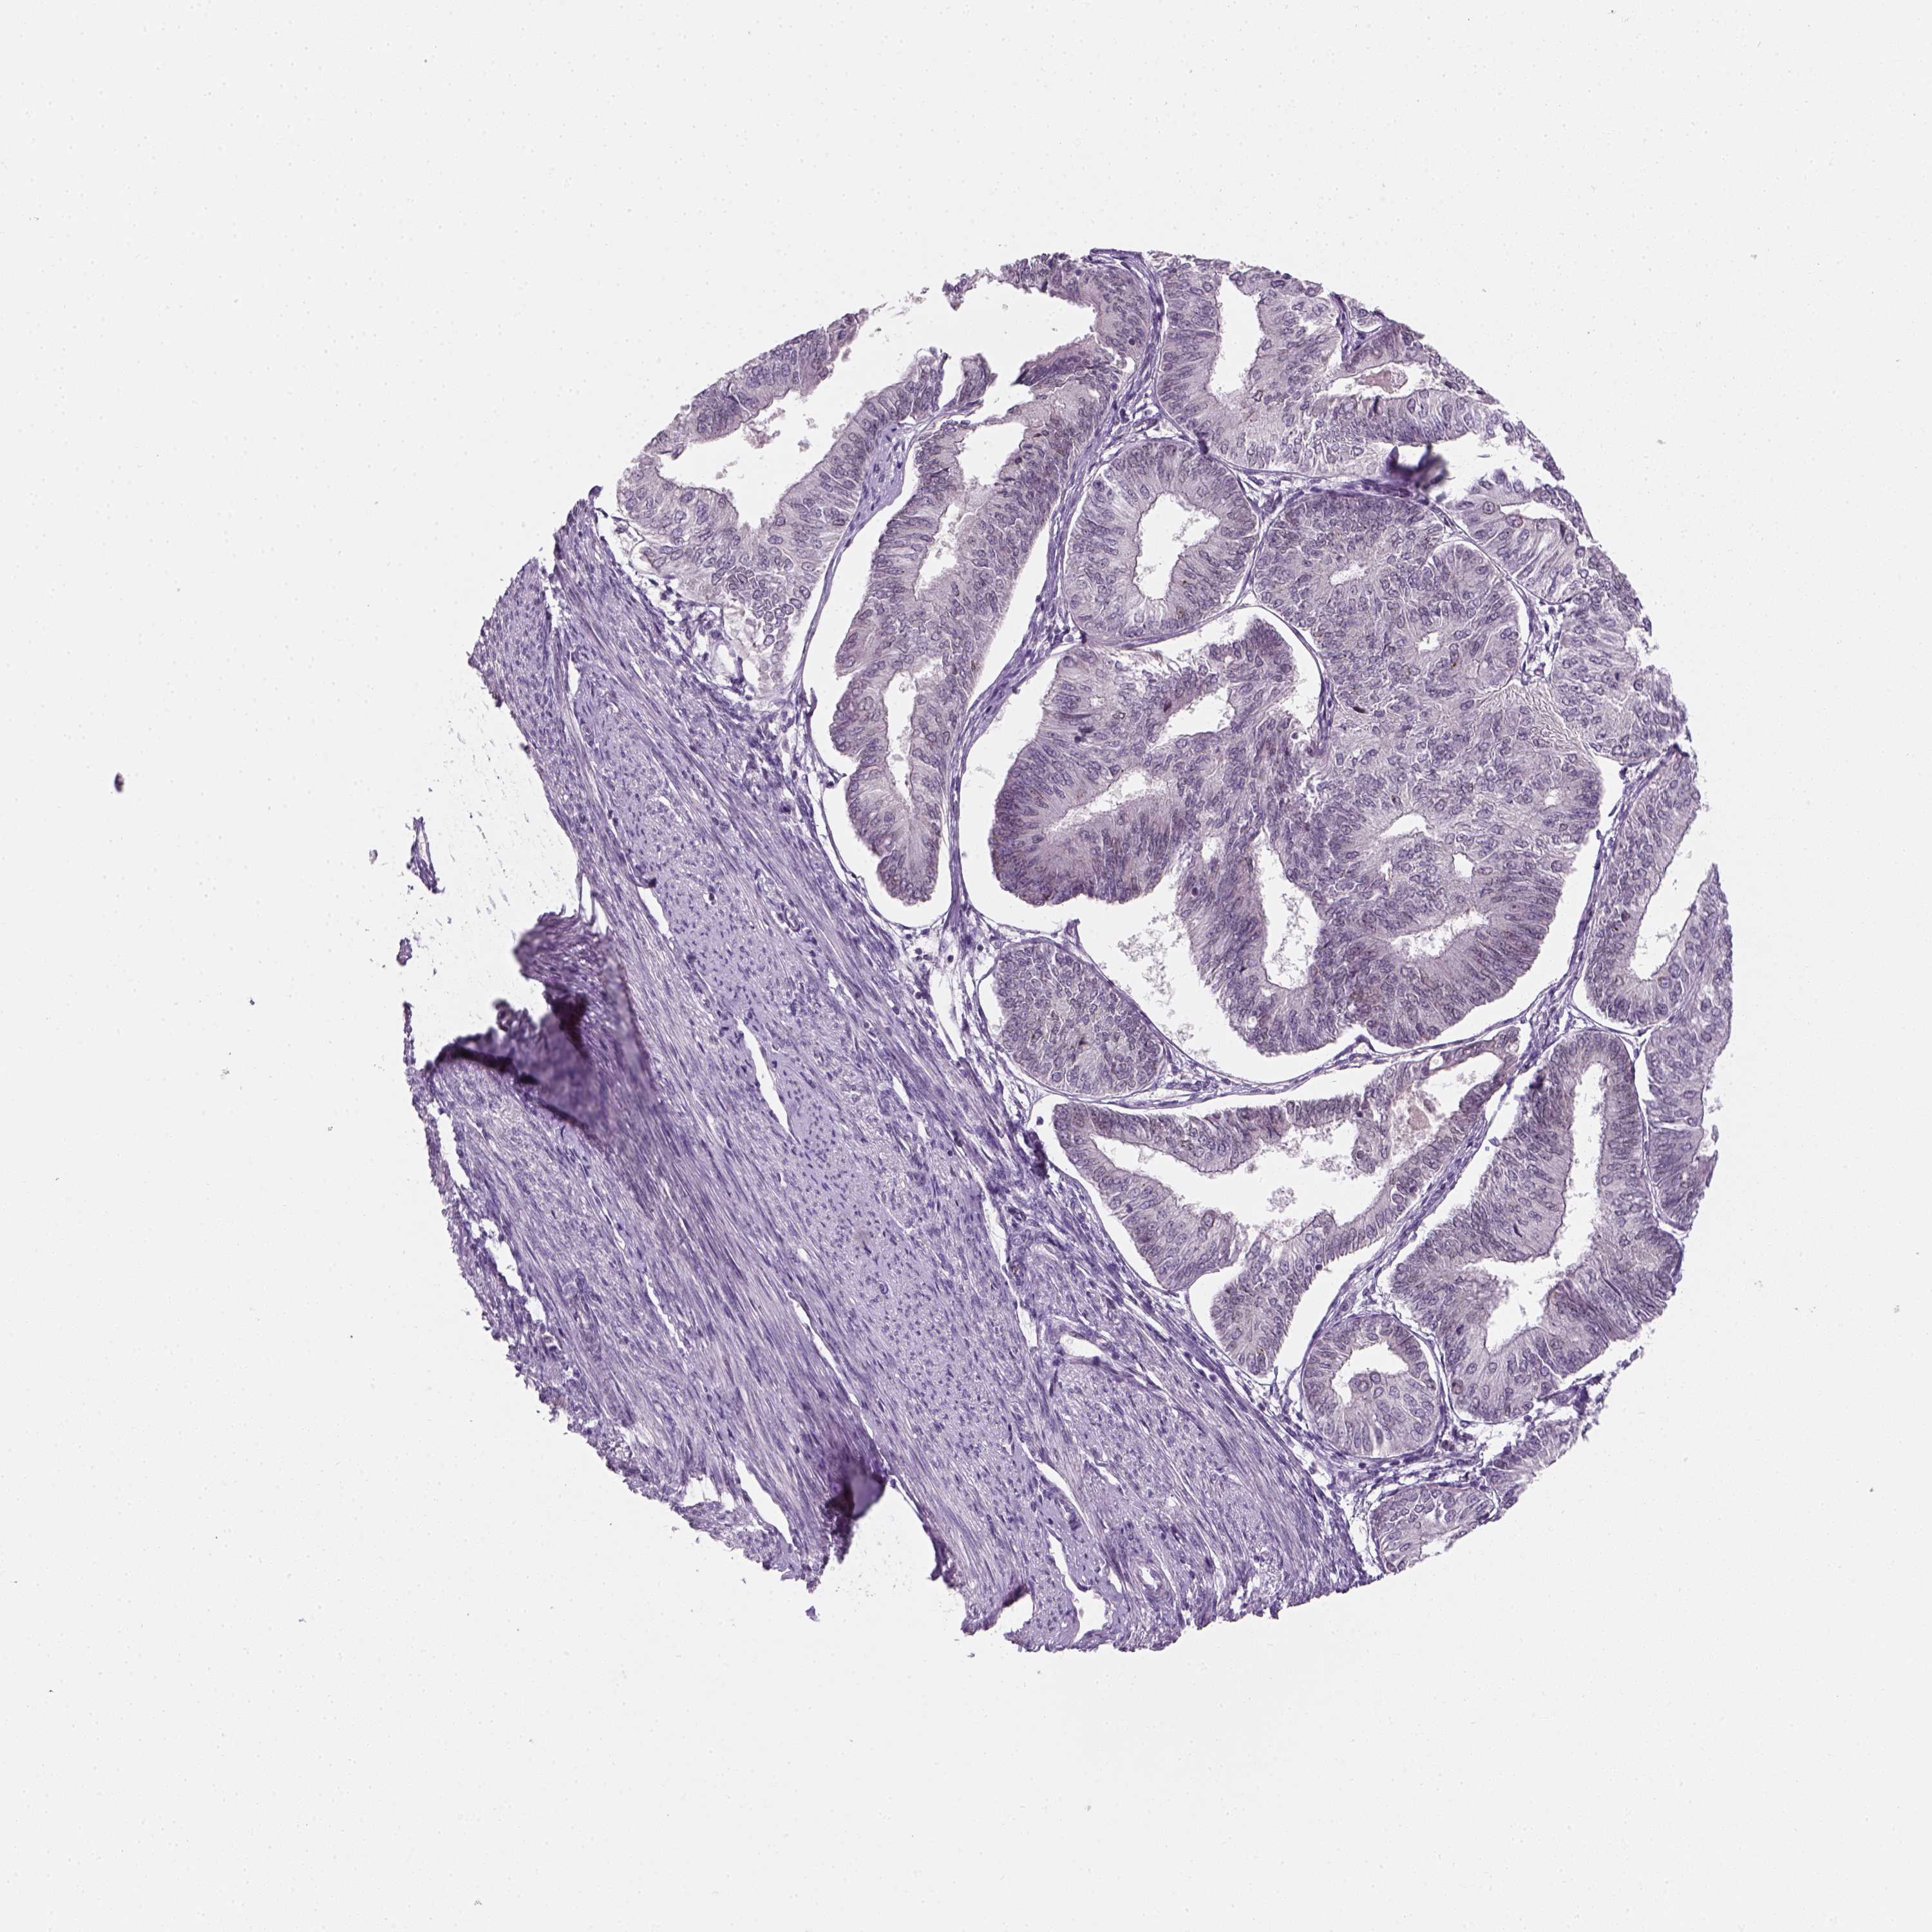

ENDOMETRIAL CANCER - Protein expressioni

A mouse-over function shows sample information and annotation data. Click on an image to view it in a full screen mode. Samples can be filtered based on level of antibody staining by selecting one or several of the following categories: high, medium, low and not detected. The assay and annotation is described here.

Note that samples used for immunohistochemistry by the Human Protein Atlas do not correspond to samples in the TCGA dataset.

Antibody stainingi

Antibody staining in the annotated cell types in the current human tissue is reported as not detected, low, medium, or high, based on conventional immunohistochemistry profiling in selected tissues. This score is based on the combination of the staining intensity and fraction of stained cells.

Each image is clickable and will lead to virtual microscopy that enables deeper exploration of all samples and also displays staining intensity scores, fraction scores and subcellular localization as well as patient and tissue information for each sample.

Antibody CAB002973

Antibody CAB039238

Antibody CAB039239

Antibody CAB072876

Staining

High

Medium

Low

Not detected

Intensity

Strong

Moderate

Weak

Negative

Quantity

>75%

75%-25%

<25%

None

Location

Nuclear

Cytoplasmic/membranous

Cytoplasmic/membranous,nuclear

Adenocarcinoma, NOS

Neoplasm, malignant, NOS

Adenocarcinoma, metastatic, NOS